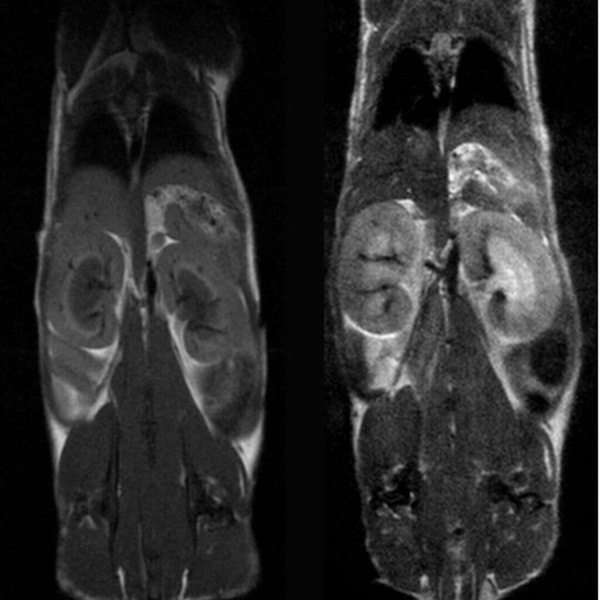

Hindlimb tumor growth: Monitoring the growth of xenograft tumor grown in the mouse hindlimb is identified with T2-weighted images. Segmentation of tumor region of interests (in red) on each tumor-containing slice allows accurate volume quantification.

Hindlimb tumor growth: Monitoring the growth of xenograft tumor grown in the mouse hindlimb is identified with T2-weighted images. Segmentation of tumor region of interests (in red) on each tumor-containing slice allows accurate volume quantification. Image Credit: Scintica Instrumentation Inc

Monitoring the growth of xenograft tumor grown in the mouse hindlimb is identified with T2-weighted images. Segmentation of tumor region of interests (in red) on each tumor-containing slice allows accurate volume quantification

Monitoring the growth of xenograft tumor grown in the mouse hindlimb is identified with T2-weighted images. Segmentation of tumor region of interests (in red) on each tumor-containing slice allows accurate volume quantification. Image Credit: Scintica Instrumentation Inc